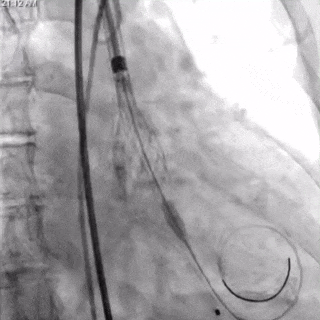

TaurusNXT植入过程:

瓣膜第一次展开与回收

瓣膜再次定位与展开

瓣膜稳定释放